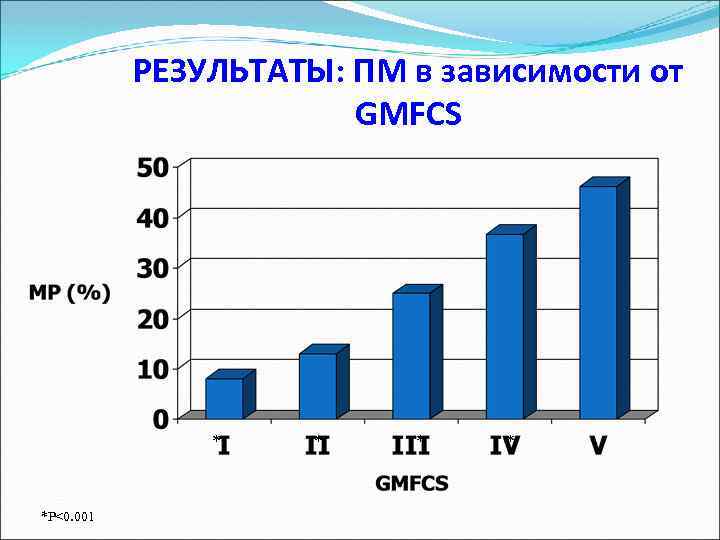

Частота встречаемости Подвывих и вывих бедра вторая по частоте патология при ДЦП (первая – эквинусная деформация голеностопных суставов) Частота варьирует в зависимости от тяжести заболевания в соответствие с уровнями классификации двигательной функции (GMFCS)

Вывих бедра при ДЦП 1. Напрямую зависит от уровня GMFCS 2. Не связан с выраженностью спастичности Спастический Дистонический Частота Смешанный Гипотонический

Вывих бедра и GMFCS Soo et al. , JBJS 2006

РЕЗУЛЬТАТЫ: ПМ в зависимости от GMFCS * *P<0. 001 * * *